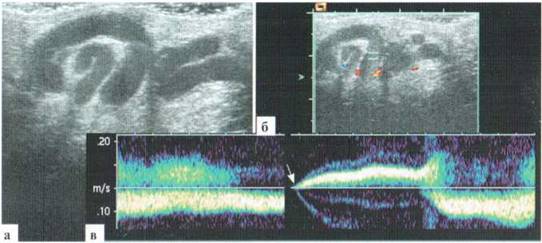

При успешной фиксации спектра кровотока определяется изменение его направления, продолжающееся несколько секунд (рис. 3.8). Скорость кровотока в варикозно расширенных венах гроздьевидного сплетения в состоянии покоя в клиностазе может быть минимальной и практически не фиксироваться (см. рис. 3.7), а при пробе Вальсальвы — достигать 10—20 см/сек.

Рис. 3.8. Донплерография при варикоцеле: а - В-режим: дилатация и резкая извитость вен; б, в — при допплерографии определяется реверсный кровоток в вене гроздьевидного сплетения. Начало реверсного кровотока (стрелка) сопровождается сбоем шкалы из-за движения ребенка